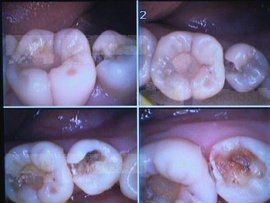

1.視診:臨床上可見很深的齲洞。

2.探診:探針可探查洞底在牙本質深層,探之極敏感或疼痛。

3.X線檢查:齲壞處可見黑色陰影。4.有條件者可用光纖維透照。